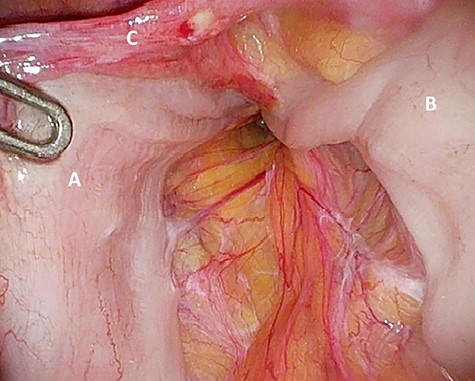

‘Loop’ of sigmoid colon in left inguinal canal (afferent loop: A; efferent loop: B; peritoneum: C).

The patient agreed to proceed with diagnostic laparoscopy for a re-re-repair of the left inguinal hernia. Intraoperatively, a loop of the sigmoid colon, which previously was hidden by colonic adhesions, was fixed into a hernia orifice lateral–caudal of the preperitoneal mesh (Fig. 4). After reopening of the peritoneum and removal of the mesh, extensive preperitoneal preparation revealed the hernia orifice located in dense scar tissue not being dissected previously (Fig. 5). A new mesh (BARD® 3D Light Mesh 12 × 17 cm) was inserted and fixed medially at the Cooper’s ligament.